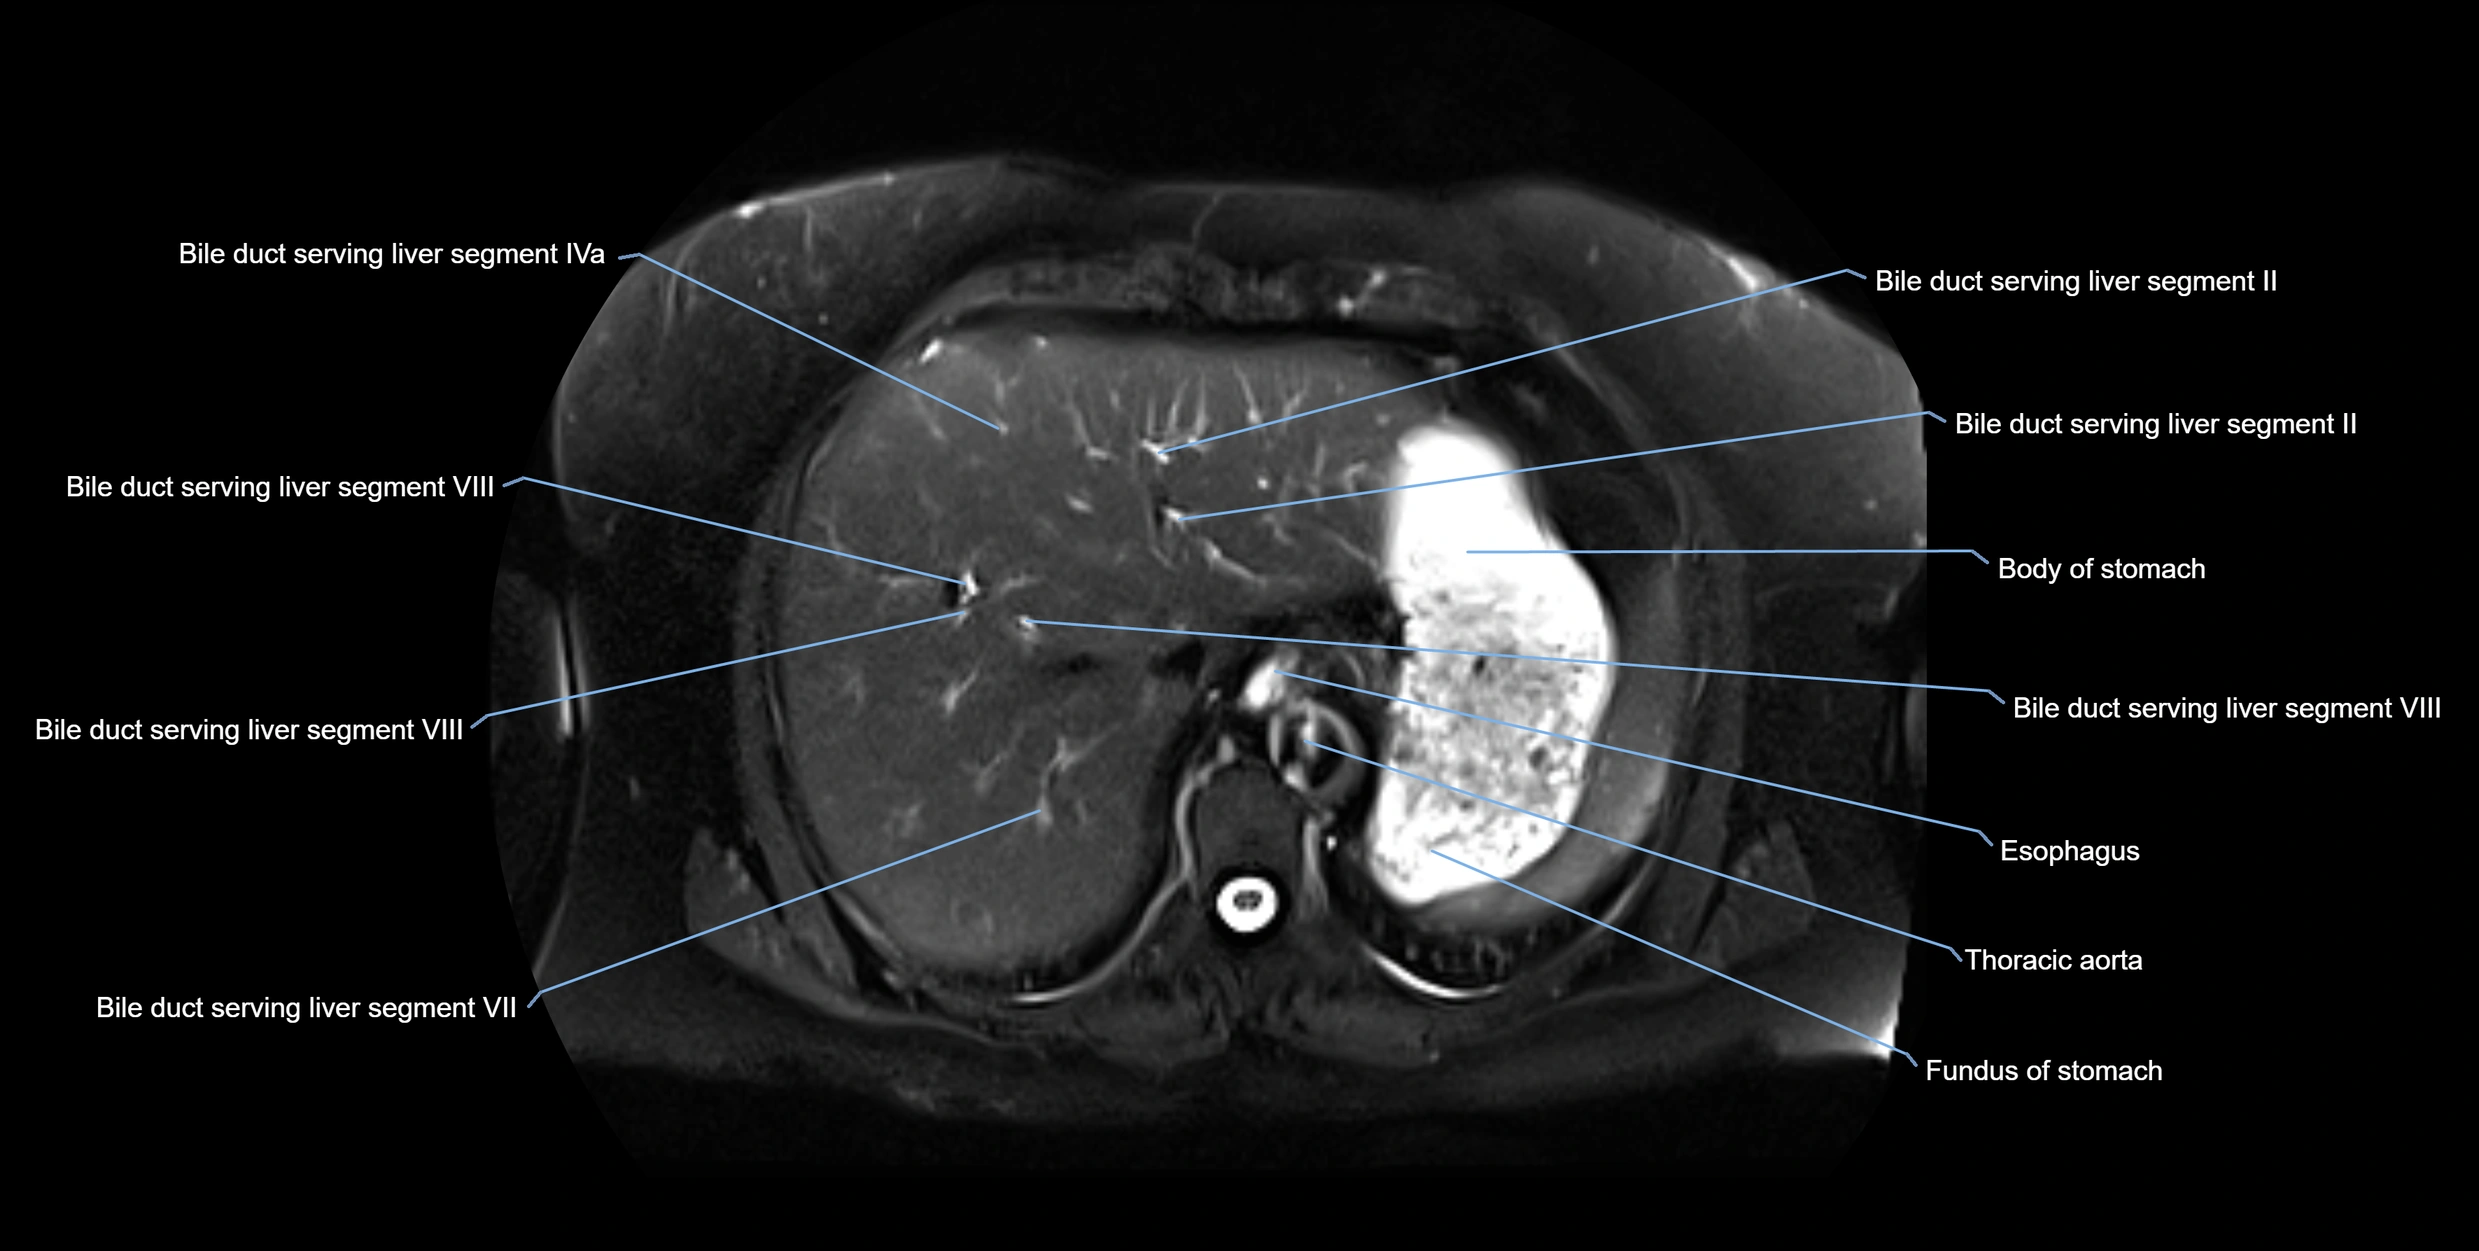

MRI Appearance

T1-weighted images:

• Not typically visualized unless dilated; appears as low signal tubular structure if seen

• Surrounding pancreatic parenchyma shows intermediate signal

T2-weighted images:

• Duct fluid appears bright

• Accessory duct seen as a fine high-signal tubular structure in pancreatic head

STIR (Short Tau Inversion Recovery):

• Duct fluid remains bright

• Surrounding fat suppressed, improving duct conspicuity

T1 Fat-Sat Post-Contrast:

• Normal duct does not enhance

• Surrounding inflammatory or neoplastic changes may enhance

T2 Fat-Saturated HASTE (single-shot):

• Accessory duct: bright, thin linear structure in pancreatic head

• Stones, strictures, or air bubbles appear as dark filling defects

• Excellent for rapid evaluation of duct patency

MRI image

image

Fullscreen Image